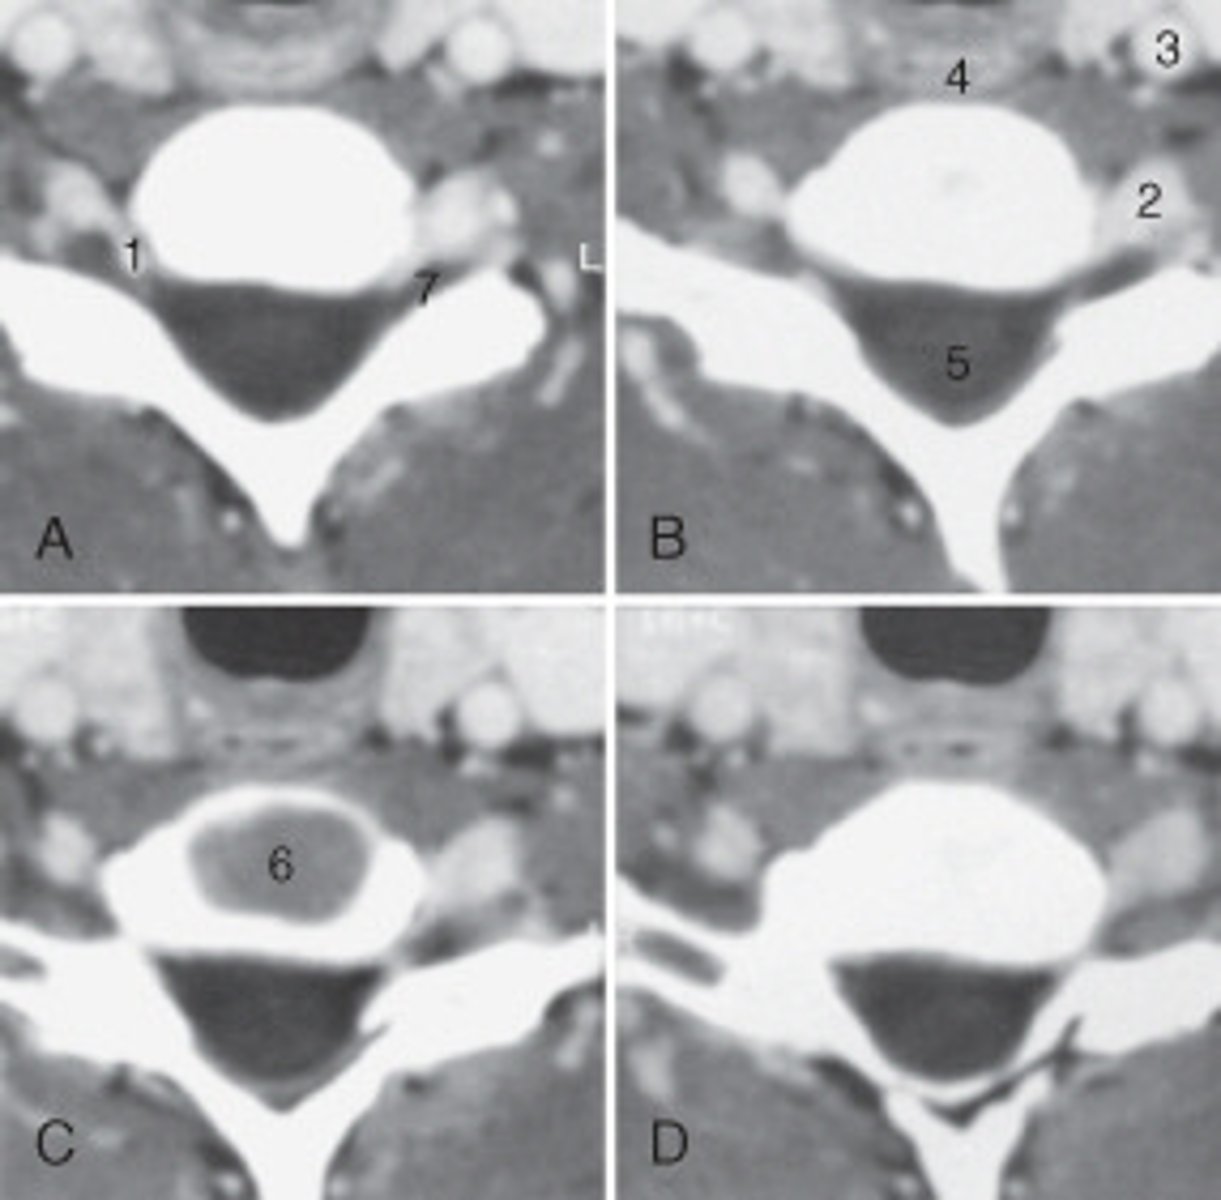

The structure labeled as 1 is the:

<p>The structure labeled as 1 is the:</p>

The thyroid cartilage is labeled:

<p>The thyroid cartilage is labeled:</p>

The common carotid artery is labeled:

<p>The common carotid artery is labeled:</p>

The structure labeled as 5 is the:

<p>The structure labeled as 5 is the:</p>

the intervertebral disk is labeled:

<p>the intervertebral disk is labeled:</p>

The structure labeled as 4 is the:

<p>The structure labeled as 4 is the:</p>